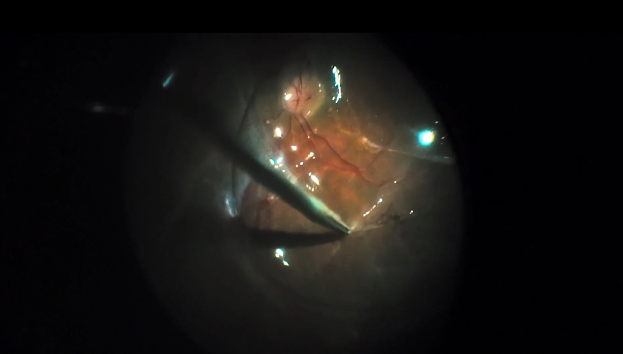

Viscodissection for Tractional Retinal Detachment

J. Daniel Diaz, MD

Severe Diabetic Tractional Retinal Detachment

Hudson Nakamura, MD

Tractional and Rhegmatogenous Retinal Detachment (3D)

Maria H. Berrocal, MD